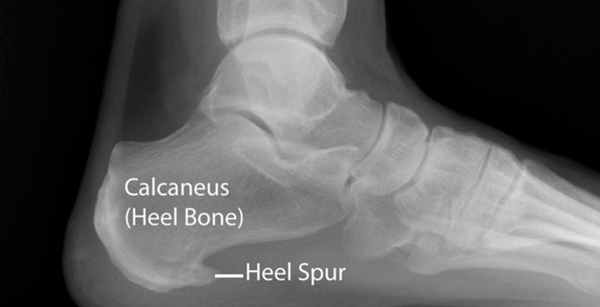

Пяточная шпора представляет собой остеофит пяточной кости. Этиологией шпор является наследственность, нарушения обмена веществ, туберкулез, ревматоидный артрит и системные воспалительные заболевания. К буграм пяточной кости прикрепляется множество мышц и подошвенная фасция, которые оказывают тракционное усилие на кость. Если пяточная шпора располагается на задней поверхности пяточной кости, то это дорсальная пяточная шпора, если она находится по подошвенной поверхности, то это подошвенная пяточная шпора. Дорсальные шпоры часто ассоциируются с тендинопатией ахиллова сухожилия, в то время как подошвенная шпора связана с подошвенным фасциитом. Вершина шпоры находится либо в месте прикрепления фасции на медиальном бугорке пяточной кости, либо в месте прикрепления мышцы короткого сгибателя пальца. Подошвенная фасция во время ходьбы претерпевает постоянное растяжение в связи с ритмичным опусканием и подъемом свода стопы, что приводит к хроническому растяжению апоневроза, которое предрасполагает к воспалительной реакции. Пронация стопы вызывает асимметричное натяжение подошвенной фасции. Избыточная пронация приводит к увеличению натяжения подошвенного апоневроза в месте прикрепления к бугру пяточной кости и считается основным механическим фактором развития подошвенной пяточной шпоры. Хроническая микротравма, которая вызывает разрывы подошвенной фасции вблизи ее прикрепления к кости, приводит к воспалению с дальнейшим развитием оссификации. Пяточная шпора прогрессирует в связи с длительным давлением на подошвенную фасцию и мышцы стопы, или растяжением подошвенной фасции вследствие избыточной подвижности 1 луча. Гиперподвижность структур медиального края стопы дает неравномерность натяжения подошвенной фасции. В области прикрепления фасции к пяточному бугру развивается хроническая микротравма и очаг воспаления, что приводит к развитию фасциита. По мере того, как воспалительный процесс приобретает черты хронического, развивается фиброз и оссификация в области пяточного бугра. Пяточная шпора может протекать либо бессимптомно, либо вызывать боль. Бессимптомные пяточные шпоры встречаются среди нормального взрослого населения в 11% случаев. Большинство пациентов с болью в пятке- это взрослые среднего возраста. У человека под пяткой появляется болезненный участок. Боль, которая локализуется в области медиального бугорка пяточной кости, вызвана давлением на подошву стопы в области прикрепления подошвенного апоневроза к пяточной кости.

Шпоры разделены по характеру течения. Во-первых, это шпоры с незначительной воспалительной реакцией с нечеткими, нерегулярными, неровными контурами с пониженной плотностью кости в области прикрепления подошвенной фасции на рентгенограмме. Они характерны для начала патологического процесса. Во-вторых, это шпоры большого размера, прогрессирование которых связано с весовой нагрузкой. Они протекают бессимптомно в связи с прекращением воспалительного процесса. В-третьих, это большие шпоры, которые вызывают боль в связи с постоянной нагрузкой, вызванной продольным или поперечным плоскостопием, вальгусом пятки и гиперпронацией стопы.

Рис. 7. Рентгенограмма стоп. Пяточная шпора